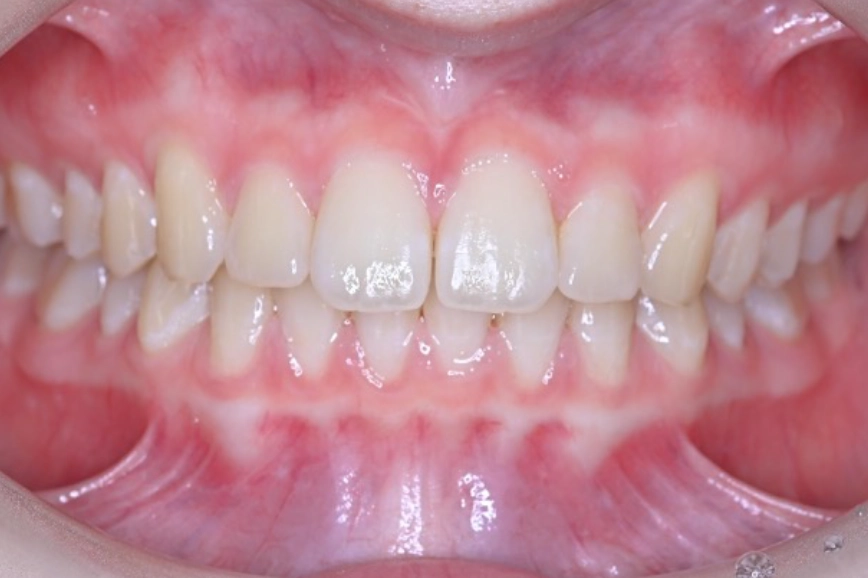

マウスピース矯正の症例

治療前

治療中

治療後

| 治療名 | 上唇小帯切除術、 アライナー矯正治療 |

| 患者様情報 | 10代 女性 |

| 担当医 | 高橋 隼平 先生 |

| 費用 | 800,000円 (税込) |

| 主訴 | 見た目が気になっている。上の前歯は歯ブラシが当たると少し痛い。 |

| 治療期間 | 約1年6ヶ月 (約2~3ヶ月に 1回ペース) |

| 治療内容 | 見た目が気になり、上の前歯は歯ブラシが当たると少し痛いとのことで来院されました。 上唇小帯については、上唇小帯切除術し、傷口が治癒した後は、インビザラインにて矯正治療を行いました。 |

| 治療のリスク | 矯正治療後、保定装置をしっかり使わないと後戻りする可能性があります。 |